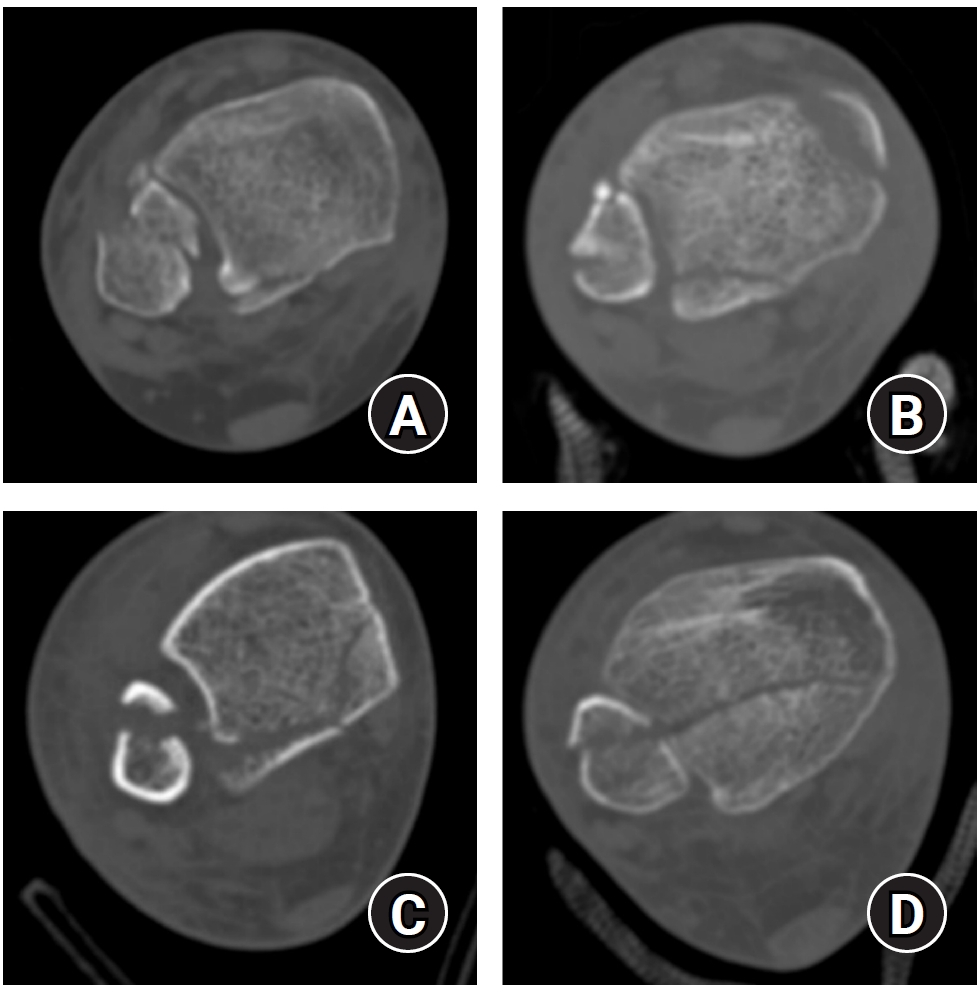

Regarding posterior malleolar fracture morphology, Haraguchi type III (small shell fragment) was more common in the <4.5 cm group, while type II (medial extension) predominated in the ≥4.5 cm group (P<0.001) (Table 2, Fig. 5). Similarly, the Bartonicek classification showed that type 1 (extra-incisural fragment with intact fibular notch) and type 2 (small posterolateral fragment extending into the fibular notch) were more frequent in the <4.5 cm group, whereas type 3 (posteromedial two-part fragment involving the medial malleolus) and type 4 (large posterolateral triangular fragment involving more than one-third of the notch) were predominant in the ≥4.5 cm group (P<0.001).

Fig. 2.

Haraguchi classification of posterior malleolar fractures. (A) Type I: posterolateral-oblique type. (B) Type II: medial-extension type. (C) Type III: small-shell type.

Fig. 2. Haraguchi classification of posterior malleolar fractures. (A) Type I: posterolateral-oblique type. (B) Type II: medial-extension type. (C) Type III: small-shell type.